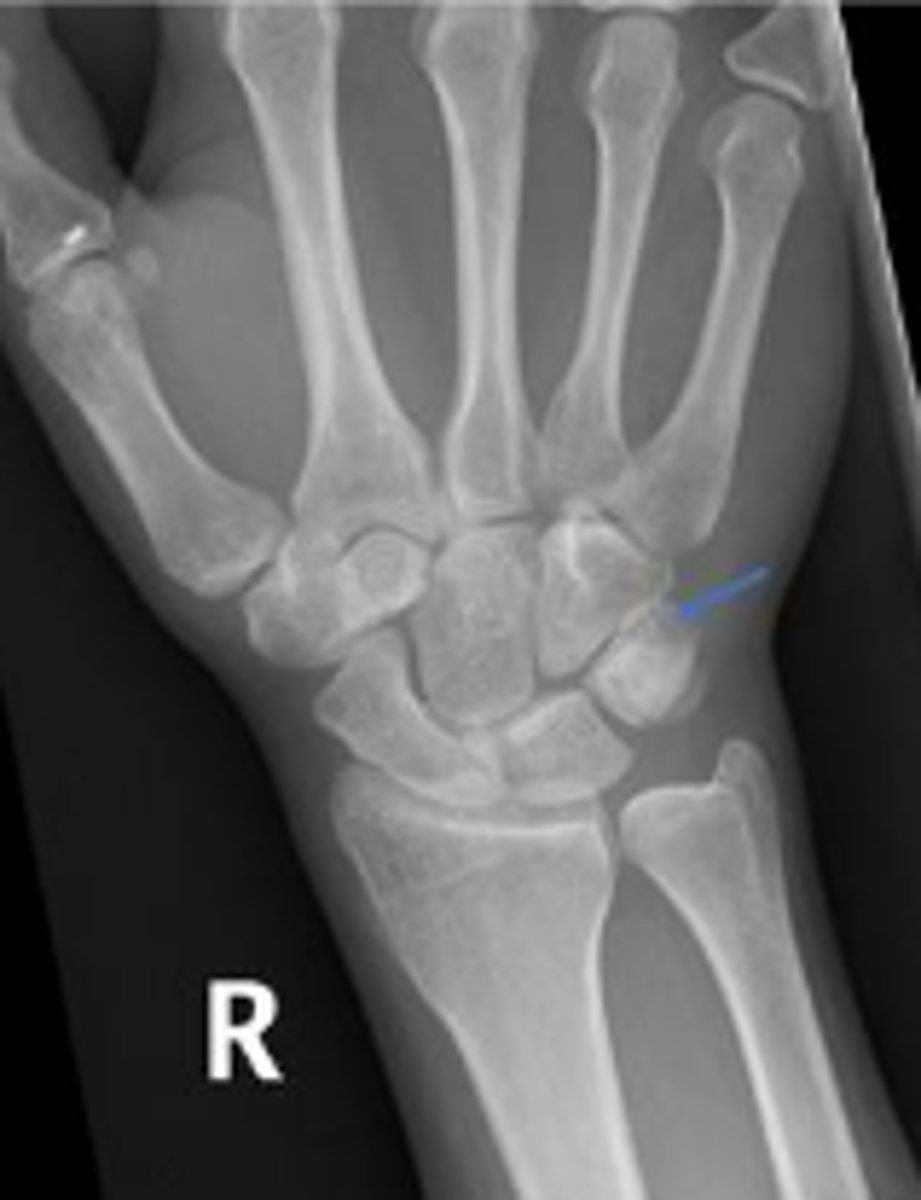

Medial oblique of the right wrist

What is the name of the radiographic view?

Right scaphoid

What is outlined?

What is the arrow pointing to?

Right trapezium

Right triquetrum

Right pisiform

What is the arow pointing to?

DRUJ

< and equal to 2mm

What is the normal measurement of this space?

Right trapezoid

Right capitate